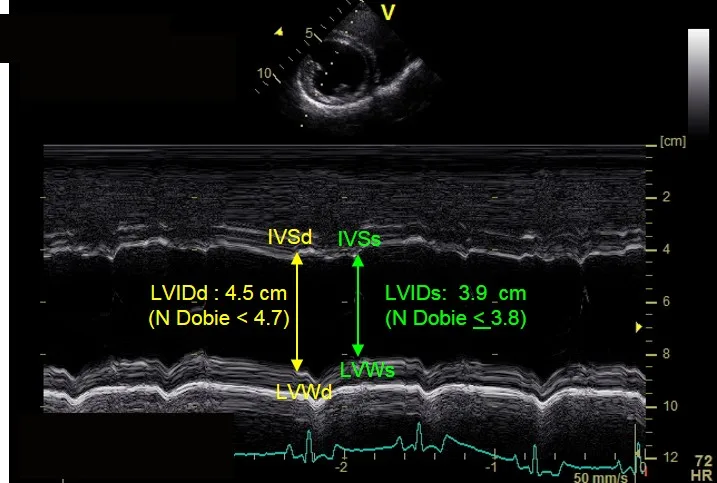

This Doberman pinscher was diagnosed with Stage B1 DCM, based on a ventricular premature contraction identified on an ECG and mild to moderate left ventricular systolic dysfunction. Figure 3A demonstrates left ventricular dimensions that are at the upper end of published normal for the breed during diastole (LVIDd) and an abnormal end systolic dimension during systole (LVIDs).

Stage B2 DCM

This Doberman Pinscher was diagnosed with Stage B2 DCM based on abnormal left ventricular measurements. Figure 4A shows left ventricular dimensions at the upper end of published normal for the breed during diastole (LVIDd) and an abnormal end systolic dimension during systole (LVIDs).

IVSd = interventricular septum in diastole, IVSs = interventricular septum in systole, LVIDd = left ventricular internal dimension in diastole, LVIDs = left ventricular internal dimension in systole, LVWd = left ventricular posterior wall in diastole, LVWd = left ventricular posterior wall in diastole, LVWs = left ventricular posterior wall in systole

The fractional shortening between these cases is similar (15% for Figure 3A and 11% for the Figure 4A); however, the LVIDd and LVIDs are extremely different as compared with normal values for the breed.